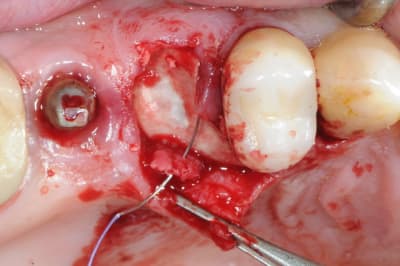

ton intervention, albert, me rappel un cas clinique que j'aimerai partager avec vous:

1-2-3 prémolaire foutu juste à proximité d'un implant, faut donc faire gaffe aux tissus environnant.

en plus je suis sure que la corticale vestibulaire est K.O elle aussi.

4-5: eh ben oui, elle est détruite! une simple curette insérée dans l'alvéole permet de visualiser l'importance de la perte osseuse vestibulaire.

que faire ??

1- curette en appuie sur la face vestibulaire montrant la destruction osseuse.

2- lambeau pleine épaisseur en palatin pour aller chercher un bout de conjonctif qui soit pédiculé.

3 je décole à partit des rebords de la déhiscence osseuse et reste en contacte permanent avec la corticale osseuse tout en décollant la gencive (elle est soulevé donc)